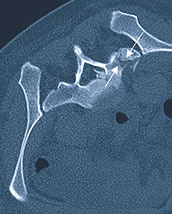

Behandlung von Blutgefäßverschlüssen Thrombose Embolie Vorbeugung einer Thrombose. Nach der körperlichen Untersuchung wird ein Röntgenbild angefertigt um den Bruch genau beurteilen und lokalisieren zu können. Die Therapie der Schmerzen am Kreuzbein hängt stark von der gestellten Diagnose ab.

Eine nicht dislozierte also nicht ausgerenkte Sakrumfraktur kann in den meisten Fällen konservativ dh. Ist tatsächlich das Steißbein gebrochen wird in der Regel konservativ behandelt.